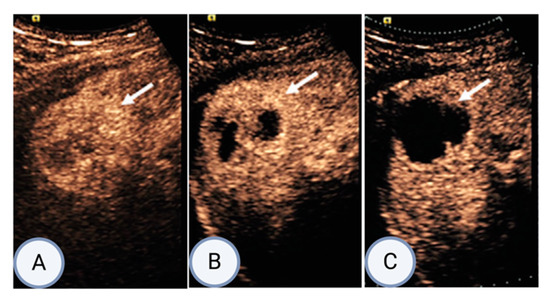

There is limited clinical evidence for the efficacy of AVUS in treating liver tumors. In the only clinical trial of AVUS for HCC, 11 patients underwent treatment with transarterial radioembolization (TARE) alone, while 17 patients received TARE along with adjuvant AVUS immediately following TARE [19]. The reported objective response rate was significantly higher in the group that received adjuvant AVUS after TARE (93%) compared to the group treated solely with TARE (50%), (p = 0.02) [19]. A representative image from this study (Figure 7) demonstrates an effective reduction in perfusion and tumor volume, visualized using CEUS [19].

Figure 7. Example series adapted from Eisenbrey et al., showing post-procedure responses in a 54-year-old male participant undergoing hepatocellular carcinoma radioembolization with US-triggered microbubble (MB) destruction [19]. The series shows peak contrast-enhanced US enhancement in targeted lesion (arrow) 2 h (A), 1 week (B), and 2 weeks (C) after combined AVUS and radioembolization therapy.

This clinical trial demonstrated the safety profile of AVUS in combination with TARE, with no hemodynamic or liver function test (LFT) changes observed 1 month after therapy [19]. Additionally, greater tumor responses were demonstrated in combined therapy, providing promising preliminary results [19]. Longer-term follow-up of participants is needed to further validate the safety of AVUS in HCC patients, and larger prospective trials are needed to establish best clinical practice in using novel AVUS in the context of HCC.